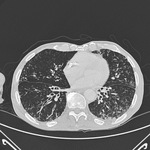

TC de tórax en la que se muestra las vías respiratorias dilatadas y engrosadas, y el patrón de ramificaciones de árbol periférico de un paciente con bronquiectasias

De la colección personal de Dr S.M. Bhorade, University of Chicago Medical Center; utilizada con autorización